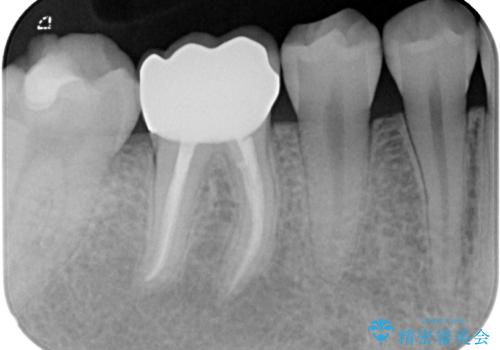

病変が消退しているかどうか、半年、1年とレントゲン写真で経過観察を行う必要があります。

海外に行かれていた都合で、術後2年での経過観察となりましたが、無事に病変の消失が認められました。